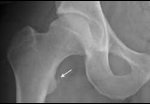

Psoas Avulsion Fracture

<div id="article-content-body"><p><img src="/sites/default/files/images/Con1PESporPAF.jpg" style="margin-right: 8px; margin-left: 8px; border: 1px solid black; float:...